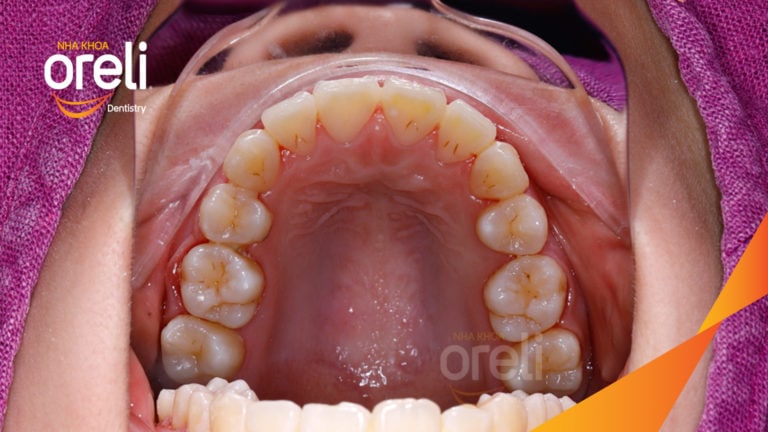

Ca niềng chỉnh chen chúc hẹp hàm nặng cả trên và dưới – Kết quả điều trị thực tế tại nha khoa Oreli Niềng răngChen chúc Xem thêm